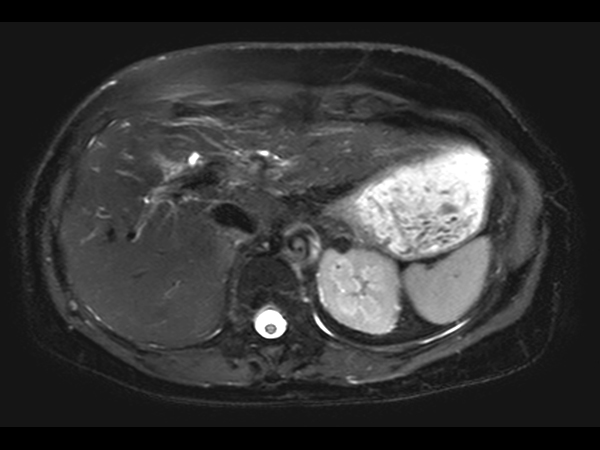

Axial mDIXON – Water (post-gado) dS SENSE = 5.6, MobiView